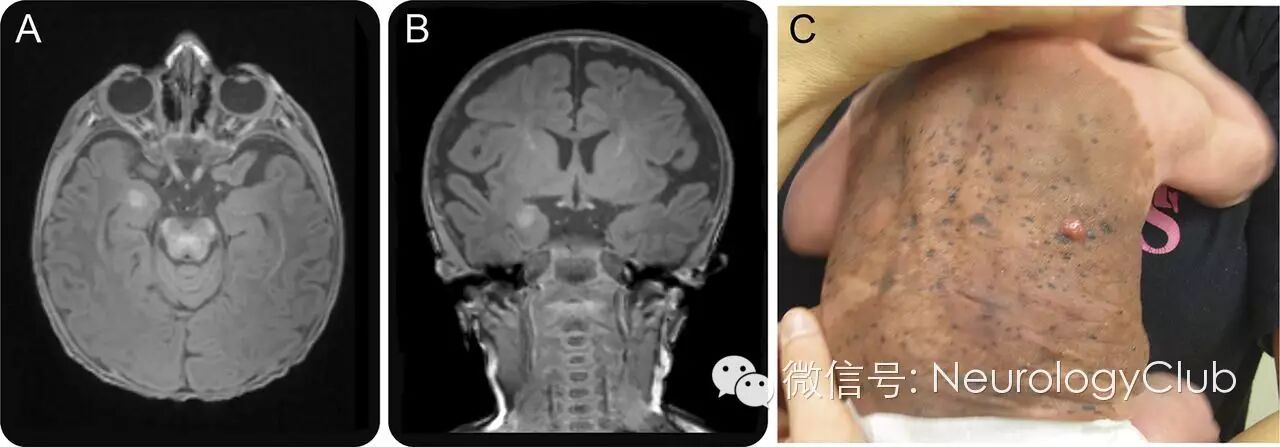

3月大男孩,背部可见巨大的先天性黑色素痣。患儿发育正常,并无明显的神经系统症状。头颅MRI提示右侧杏仁核T1高信号,不伴有坏死,出血,水肿或强化(图)。脊髓MRI无殊。临床结合影像,诊断考虑神经皮肤黑变病(neurocutaneous melanosis)。

(图 A、B:右侧杏仁核可见8mm×7mm×6mm短T1病灶;C:巨大的先天性黑色素痣)